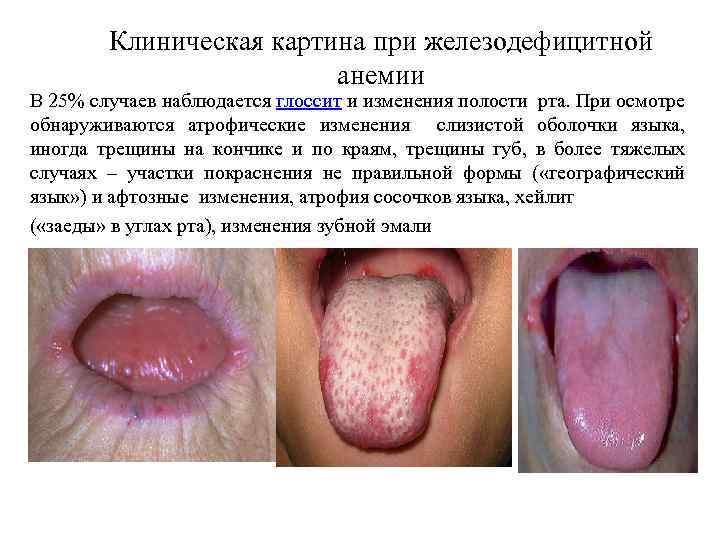

Клиническая картина при железодефицитной анемии В 25% случаев наблюдается глоссит и изменения полости рта. При осмотре обнаруживаются атрофические изменения слизистой оболочки языка, иногда трещины на кончике и по краям, трещины губ, в более тяжелых случаях – участки покраснения не правильной формы ( «географический язык» ) и афтозные изменения, атрофия сосочков языка, хейлит ( «заеды» в углах рта), изменения зубной эмали